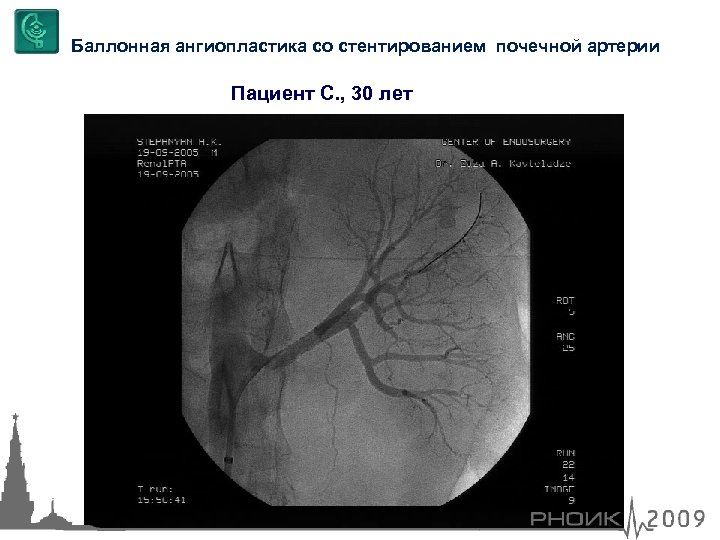

Баллонная ангиопластика со стентированием почечной артерии Пациент С. , 30 лет

Баллонная ангиопластика со стентированием почечной артерии Пациент С. , 30 лет

Баллонная ангиопластика со стентированием почечной артерии Пациент С. , 30 лет

Баллонная ангиопластика со стентированием почечной артерии Пациент С. , 30 лет